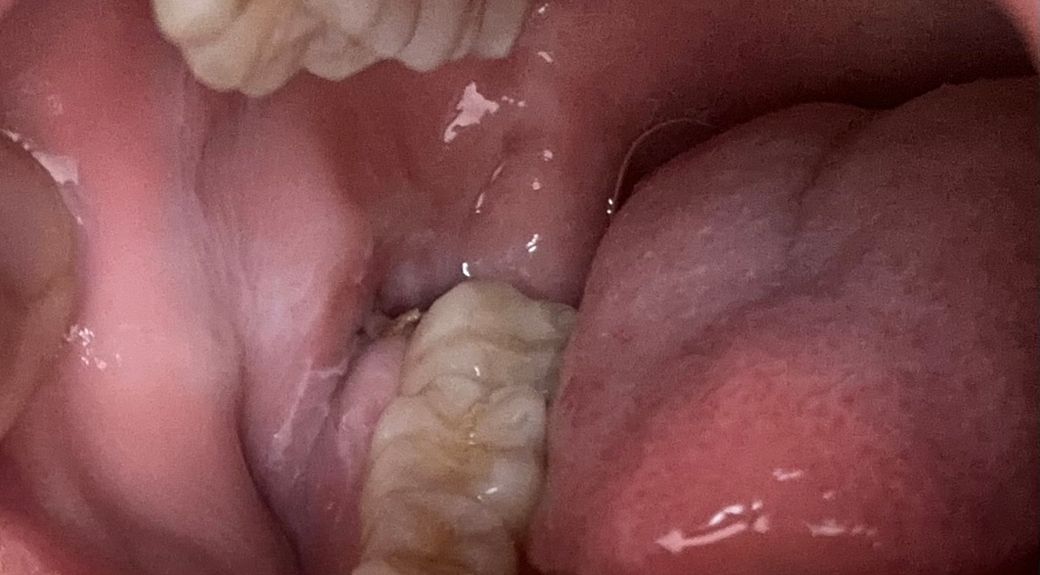

수요일에 왼쪽 아래 매복사랑니 발치하고 3일째입니다 녹는실을 쓰셨다고 치과는 다시 내원 안한다고 하셨는데 지금 염증 하나 없이 잘 낫고 있는게 맞는건가요 ?̊̈ ?̊̈

그리고 뭔가 걸리적거리는데 이게 같은건 뭘까요 여긴 가글 처방을 안해주셔서 최대한 안닿게 닦고는 있지만 ㅠㅠ 어제 삼겹살을 먹었는데 저게 삼겹살 낀건지 아님 실인지를 모르겠네요 갑자기 걸리적거리는데,,

이게 삼겹살 먹기 전인데 그냥 실인걸까요?

• 1번 째 사진

이정도면 정상적으로 아물고 있는 것입니다. 혹시 음식물 잔사가 낄 수도 있지만 그냥 두면 저절로 빠집니다.

사진상으로 보면 잘 아물고 잇는거 같으니 크게 걱정은 안하셔도 될것같습니다. 최대한 음식물만 남지 않도록 관리를 해주세요.

1. 염증의 양상은 특별히 보이지 않습니다

2. 양치질 살살 해주셔도 됩니다 음식물이 안끼어 있어야 치유가 빨리됩니다